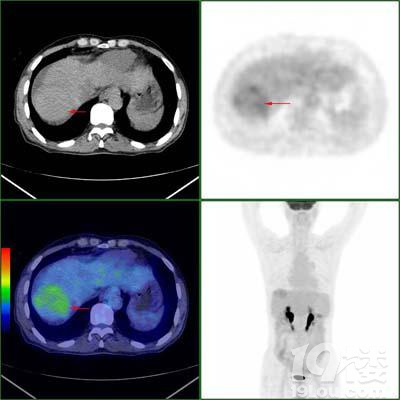

PET利用示踪剂(如氟18,碳11等),采用静脉注射等方式注入人体后,通过探测这些示踪剂/探针在体内的聚集,来反映生命代谢活动的情况,从而达到诊断的目的。以最常见的肿瘤显像为例,恶性肿瘤细胞对FDG(葡萄糖)摄取能力大大超过了正常细胞,FDG标记放射性核素后注入人体,会出现放射性核素在肿瘤等病变组织中的浓聚,从而在设备工作站的图像上会显示出一个放射性浓集的区域,结合SUV等定量信息,再结合CT传统的解剖影像提高病灶定位的准确性,帮助医生进行诊断和疗效评估等。

PET/CT显像提示肝癌